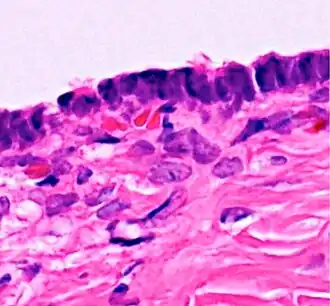

Micrograph of serous carcinoma, a type of serous tumour. |

A serous tumour is a neoplasm that typically has papillary to solid formations of tumor cells with crowded nuclei, and which typically arises on the modified Müllerian-derived serous membranes that surround the ovaries in females. Such ovarian tumors are part of the surface epithelial-stromal tumour group of ovarian tumors. They are common neoplasms with a strong tendency to occur bilaterally, and they account for approximately a quarter of all ovarian tumors.